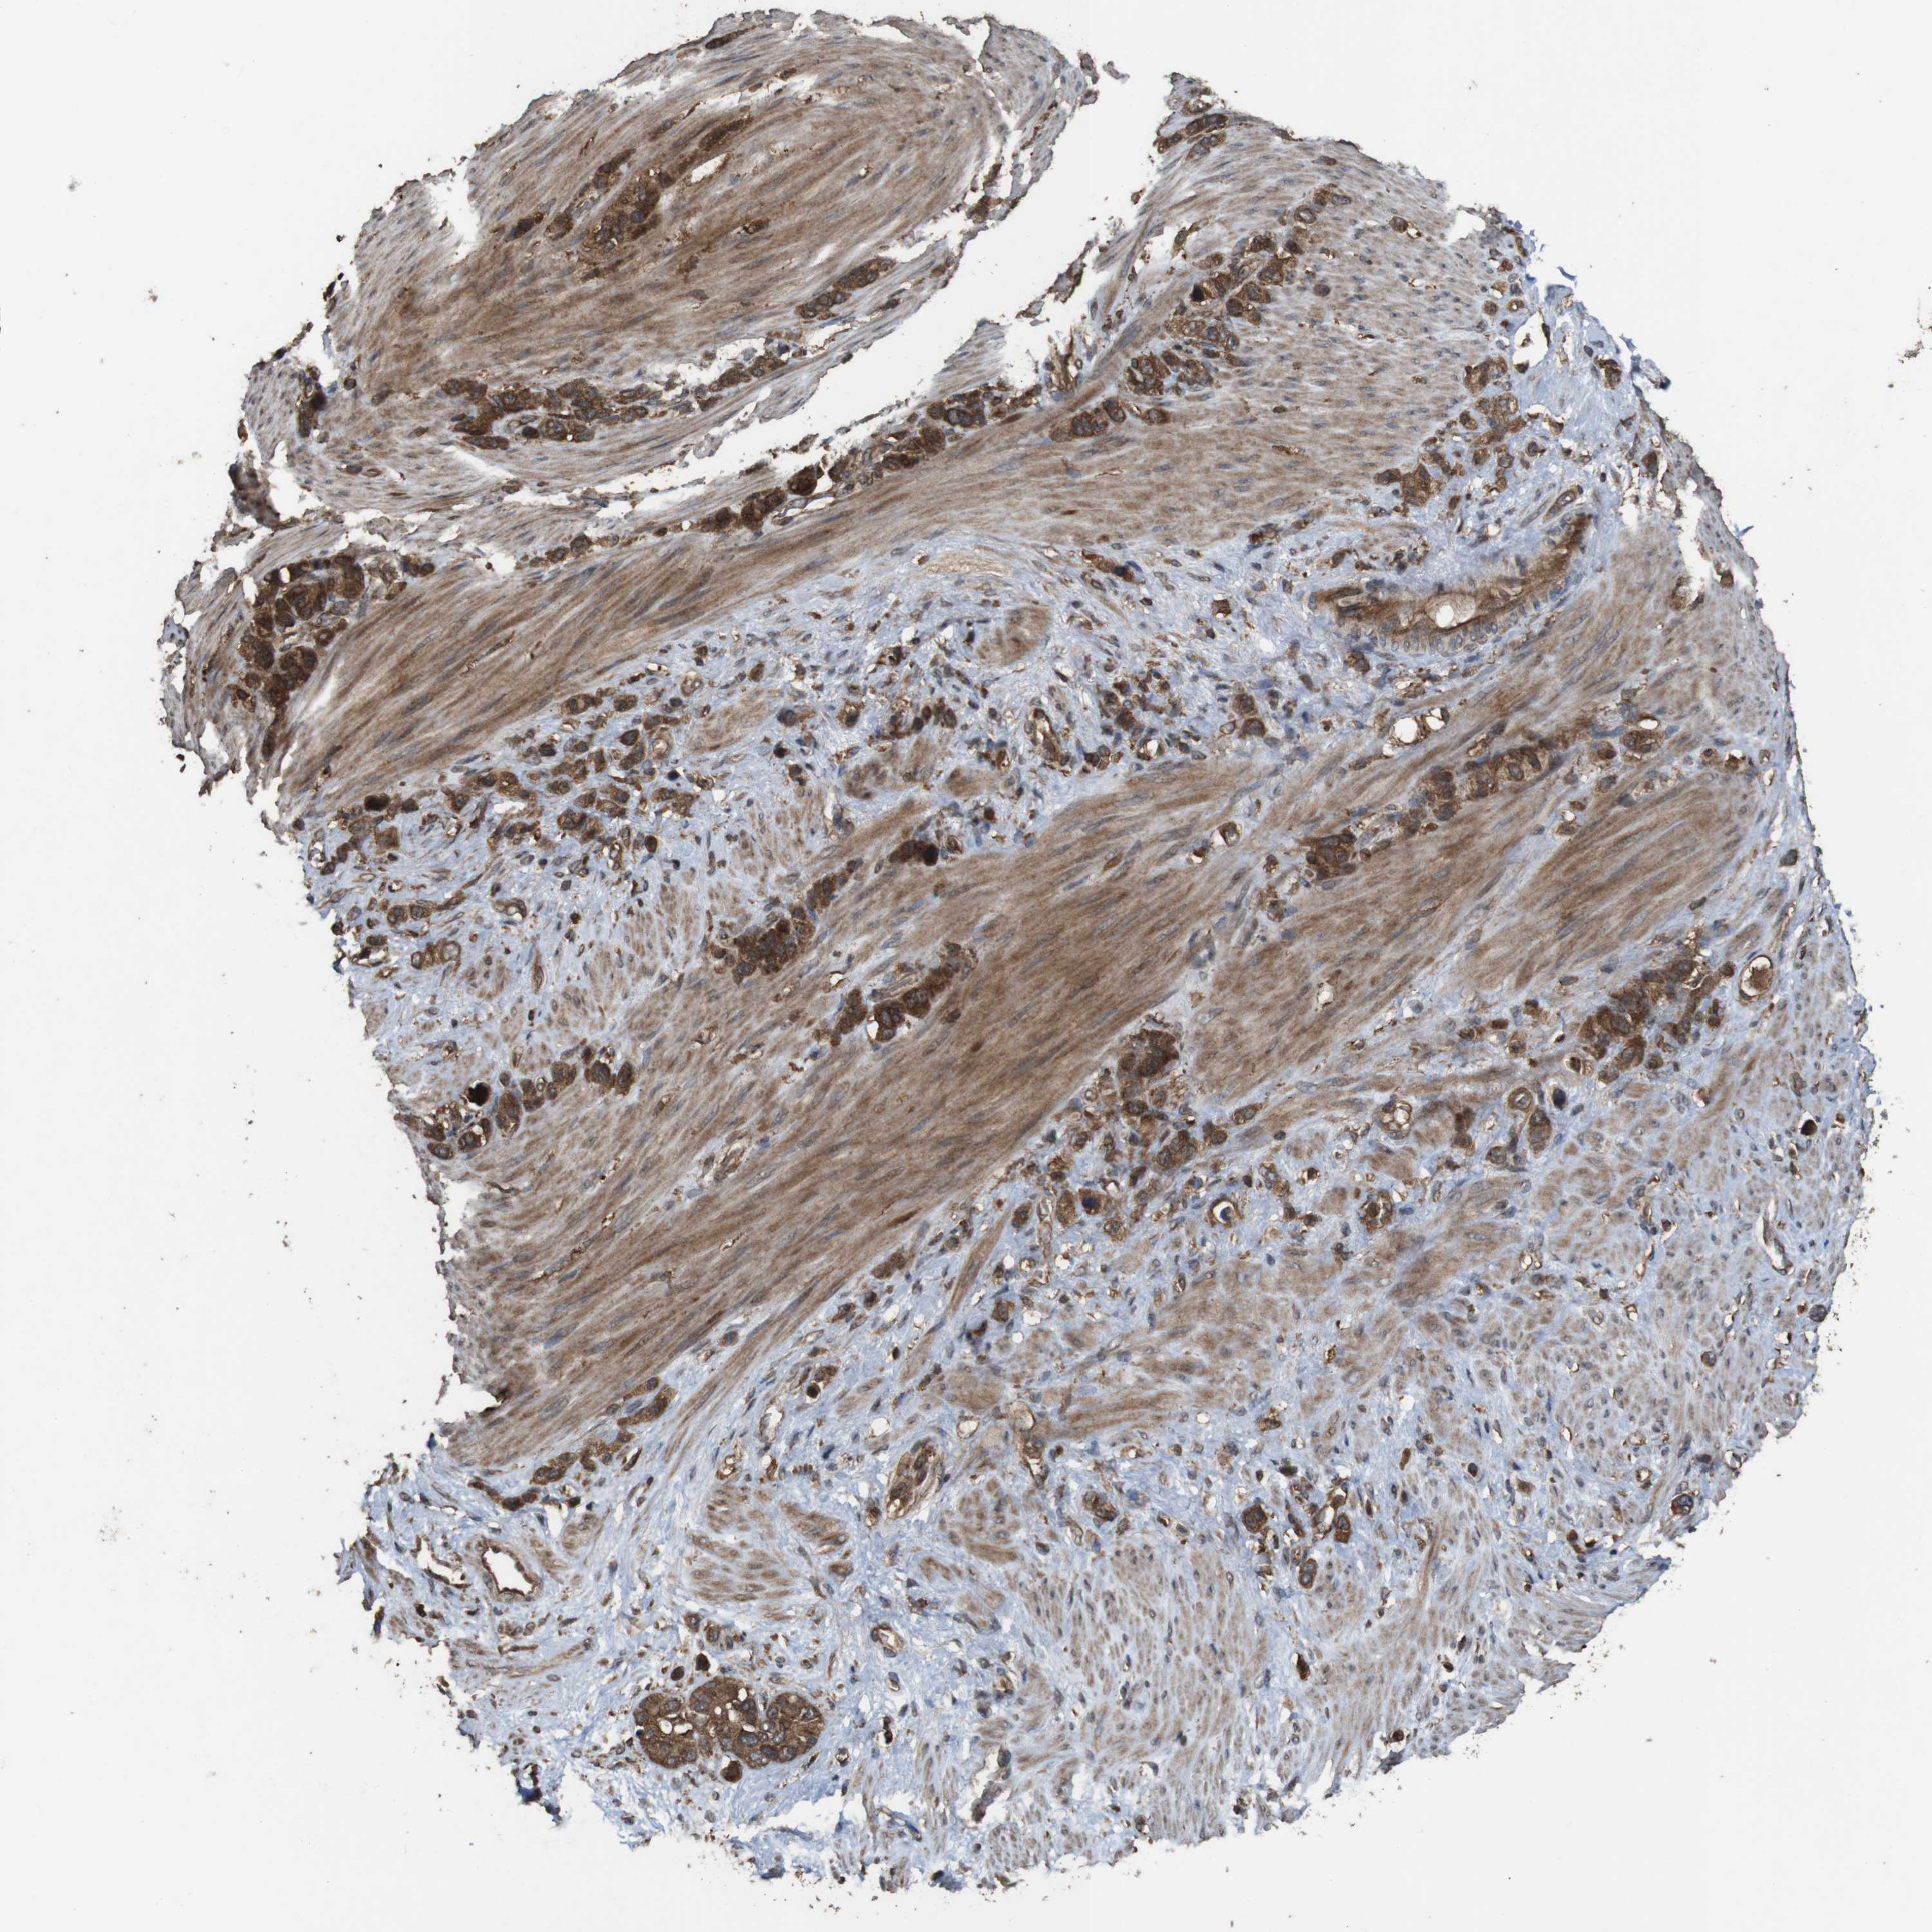

STOMACH CANCER - Protein expressioni

A mouse-over function shows sample information and annotation data. Click on an image to view it in a full screen mode. Samples can be filtered based on level of antibody staining by selecting one or several of the following categories: high, medium, low and not detected. The assay and annotation is described here.

Note that samples used for immunohistochemistry by the Human Protein Atlas do not correspond to samples in the TCGA dataset.

Antibody stainingi

Antibody staining in the annotated cell types in the current human tissue is reported as not detected, low, medium, or high, based on conventional immunohistochemistry profiling in selected tissues. This score is based on the combination of the staining intensity and fraction of stained cells.

Each image is clickable and will lead to virtual microscopy that enables deeper exploration of all samples and also displays staining intensity scores, fraction scores and subcellular localization as well as patient and tissue information for each sample.

Antibody HPA018951

Antibody CAB013716

Staining

High

Medium

Low

Not detected

Intensity

Strong

Moderate

Weak

Negative

Quantity

>75%

75%-25%

<25%

None

Location

Nuclear

Cytoplasmic/membranous

Cytoplasmic/membranous,nuclear

Adenocarcinoma, NOS

Adenocarcinoma, High grade